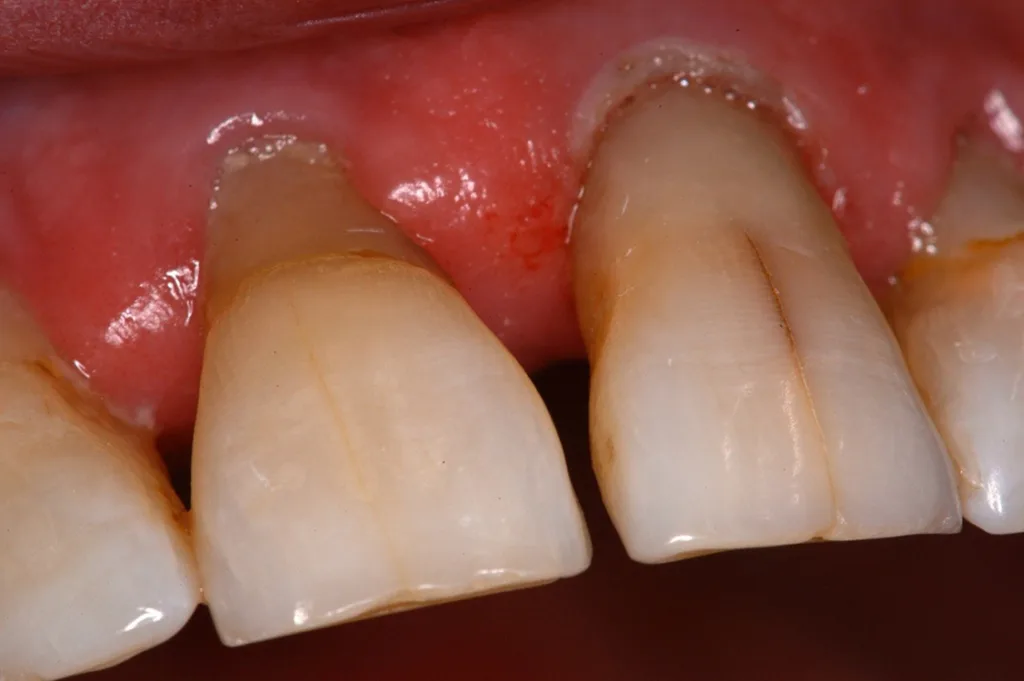

Mit zunehmendem Alter kommt es zu Veränderungen in Knochenstruktur und -metabolismus mit Abnahme der Knochendichte und -masse, reduzierter Stoffwechselaktivität, Rückgang der Zahl der Osteoblasten und Osteozyten sowie Zunahme der Osteoklastenaktivität [46]. Die Zusammensetzung und die Struktur des Dentins ändern sich mit zunehmendem Alter: Der Anteil sklerotischen Dentins nimmt zu, der Anteil kollagener Faser nimmt ab, dadurch erhöht sich die Anfälligkeit für Längsfrakturen (Abb. 1). Der Durchmesser der Dentintubuli wird geringer. Die Veränderungen in der Schmelz- und Dentinstruktur manifestieren sich auch im Verlust der Transparenz und gelblicher Zahnverfärbung sowie dem Auftreten von Schmelzrissen (Abb. 2) [46,48].